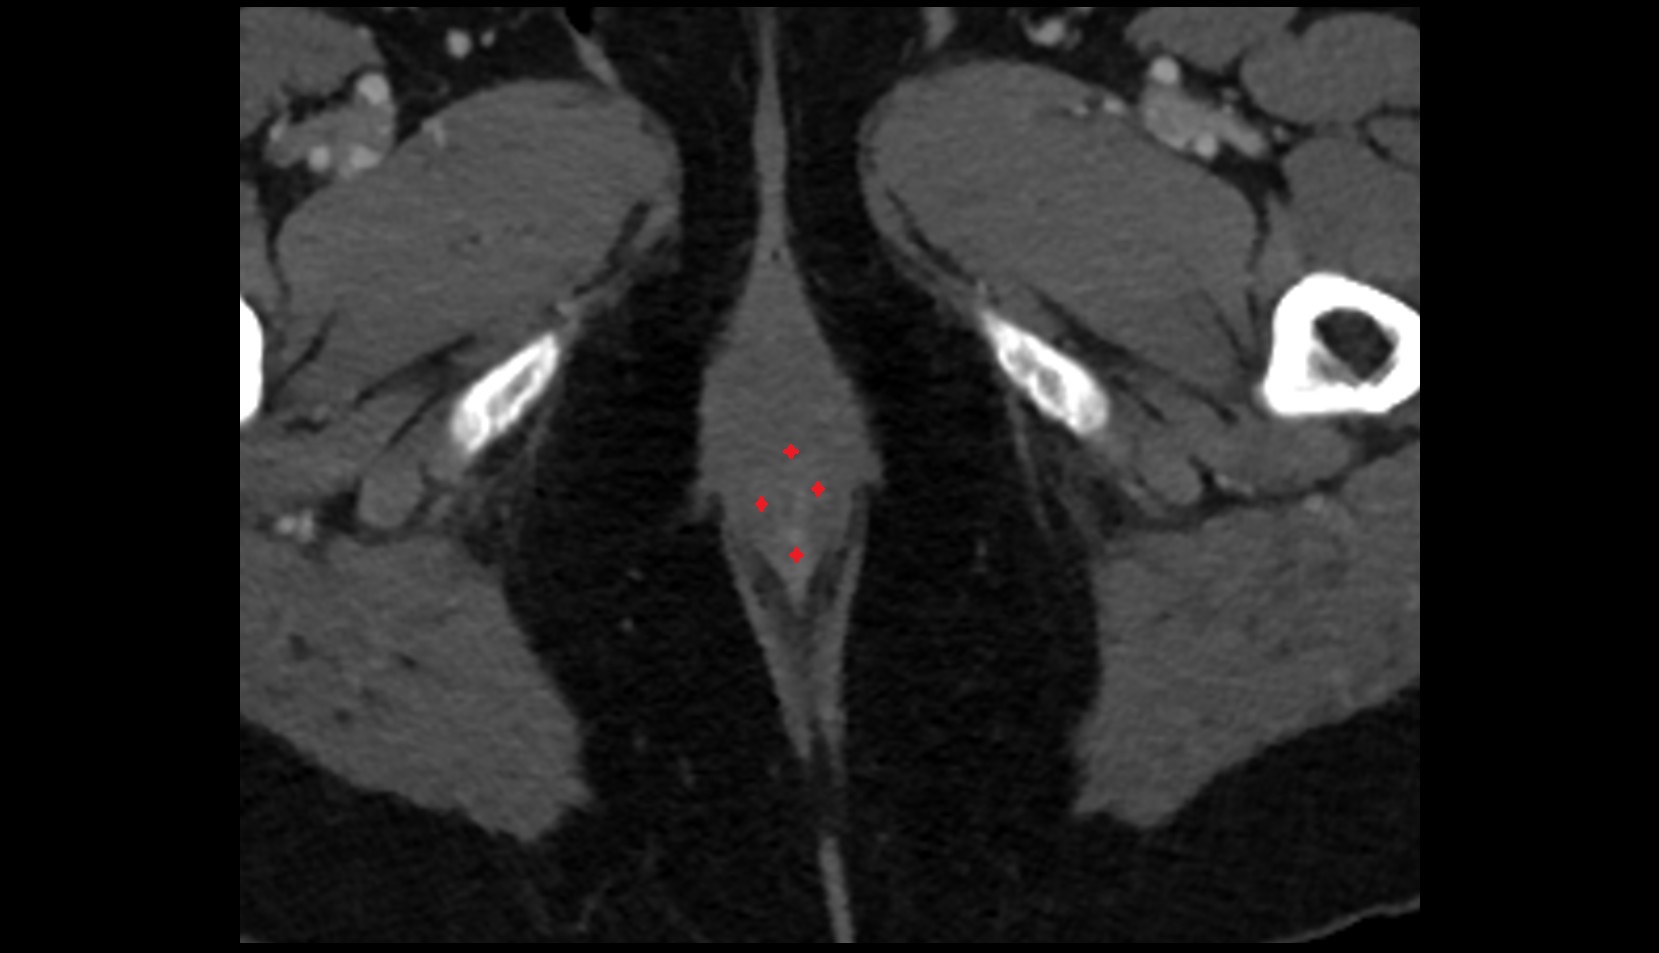

- Peripheral zone of prostate

- Anterior Fibromuscular Stroma of prostate

- Central zone of prostate

- Transitional zone of prostate